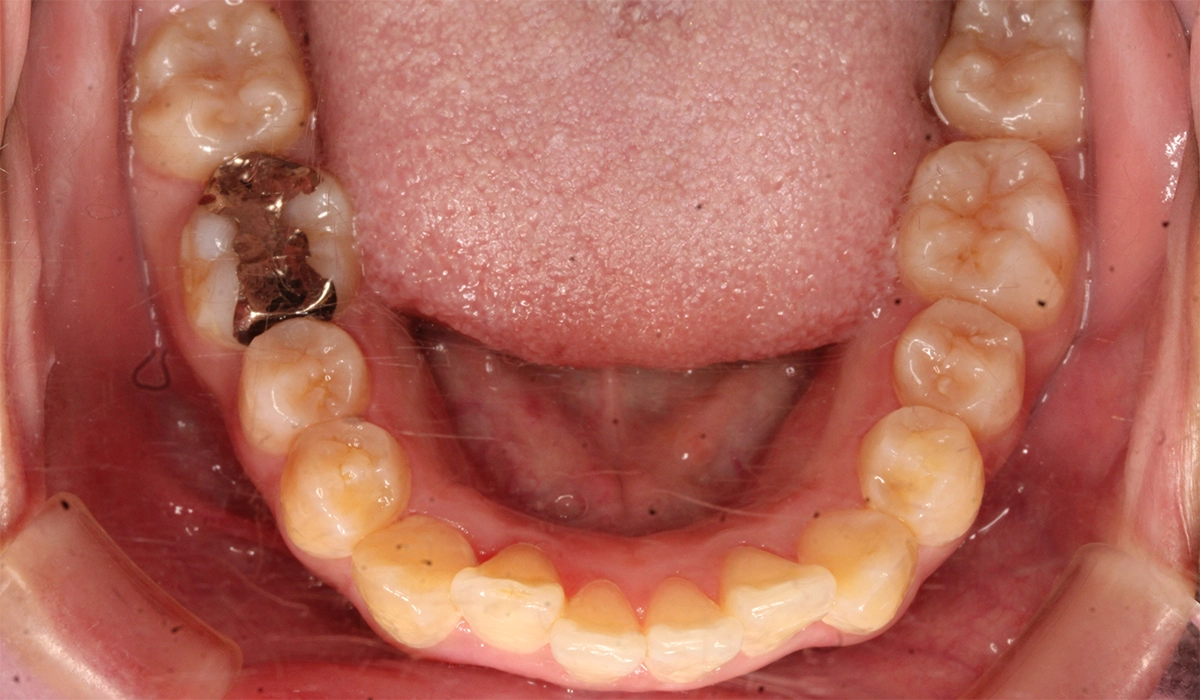

術前:下顎